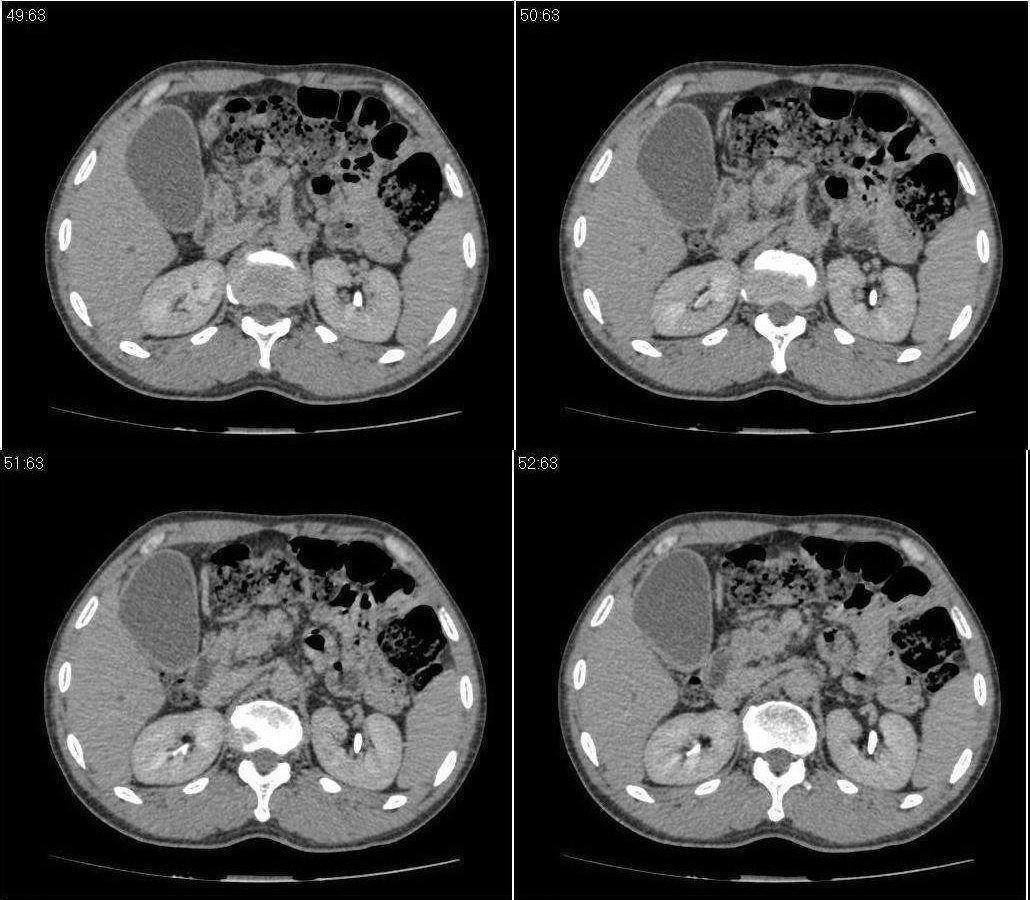

标题: CT21384:男性,50岁。发现无痛性黄疸十余天,B朝提示肝胆管 [打印本页]

标题: CT21384:男性,50岁。发现无痛性黄疸十余天,B朝提示肝胆管

1.考虑:壶腹占位病变(癌?)。

2.胆系低位梗阻:肝内外胆管扩张,胆囊增大,胰管扩张。

胰头癌伴低位胆道梗阻。

胆系低位梗阻(肝内外胆管扩张,胆囊增大,胰管扩张);考虑胰头癌或壶腹癌所致。

胰头强化欠均匀,胆胰管扩张。考虑胰头癌可能性大。

胆系低位梗阻(肝内外胆管扩张,胆囊增大,胰管扩张,钩突似有占位);考虑胰头癌